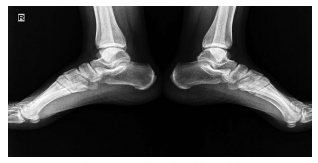

Dose reduction was used in patients with moderate and severe back pain, constituting 37.2% of the patients describing the complaint. The vast majority of these patients responded to dose reduction, while eight (10.2%) patients needed to use non-steroidal anti-inflammatory drugs for pain relief. Sacroiliitis was present in four (4%) patients, including three females and one male. There was no statistically significant difference between the sexes for sacroiliitis development (p=0.25). Bilateral sacroiliitis was detected in one patient (Figure 1). Sacroiliitis regressed 1.5 to 2.5 months after isotretinoin treatment cessation in all patients. The patients diagnosed with sacroiliitis were followed for six months. Three (3%) patients described myalgia, which was of mild severity and did not require additional treatment. Among these patients, two female patients also described low back pain. Creatine kinase (CK) elevation was observed in 18 (18.1%) patients, including 13 males and two females, one to three months after the beginning of treatment (p=0.1). The elevated CK values ranged between 233 and 940 IU and returned to normal levels after dose reduction. One (1%) female patients who was on low-dose isotretinoin treatment (0.5 mg/kg) was diagnosed with enthesitis at three months of treatment (Figure 2).

Enthesopathy is a reported side effect of isotretinoin and usually develops after long-term isotretinoin use.[37,38] However, cases associated with short-term isotretinoin treatment have also been reported in the literature. Tendinitis of the Achilles tendon is a known side effect of isotretinoin and has been reported in 9.5% of patients.4 A close relationship between Achilles tendinitis and isotretinoin dose has also been described.[39,40] In our study, the patient who developed tendinitis was on low-dose isotretinoin treatment. Dose reduction and interruption can be considered in patients developing tendinitis.[39] The symptoms of the patient in the current study regressed with the cessation of treatment.